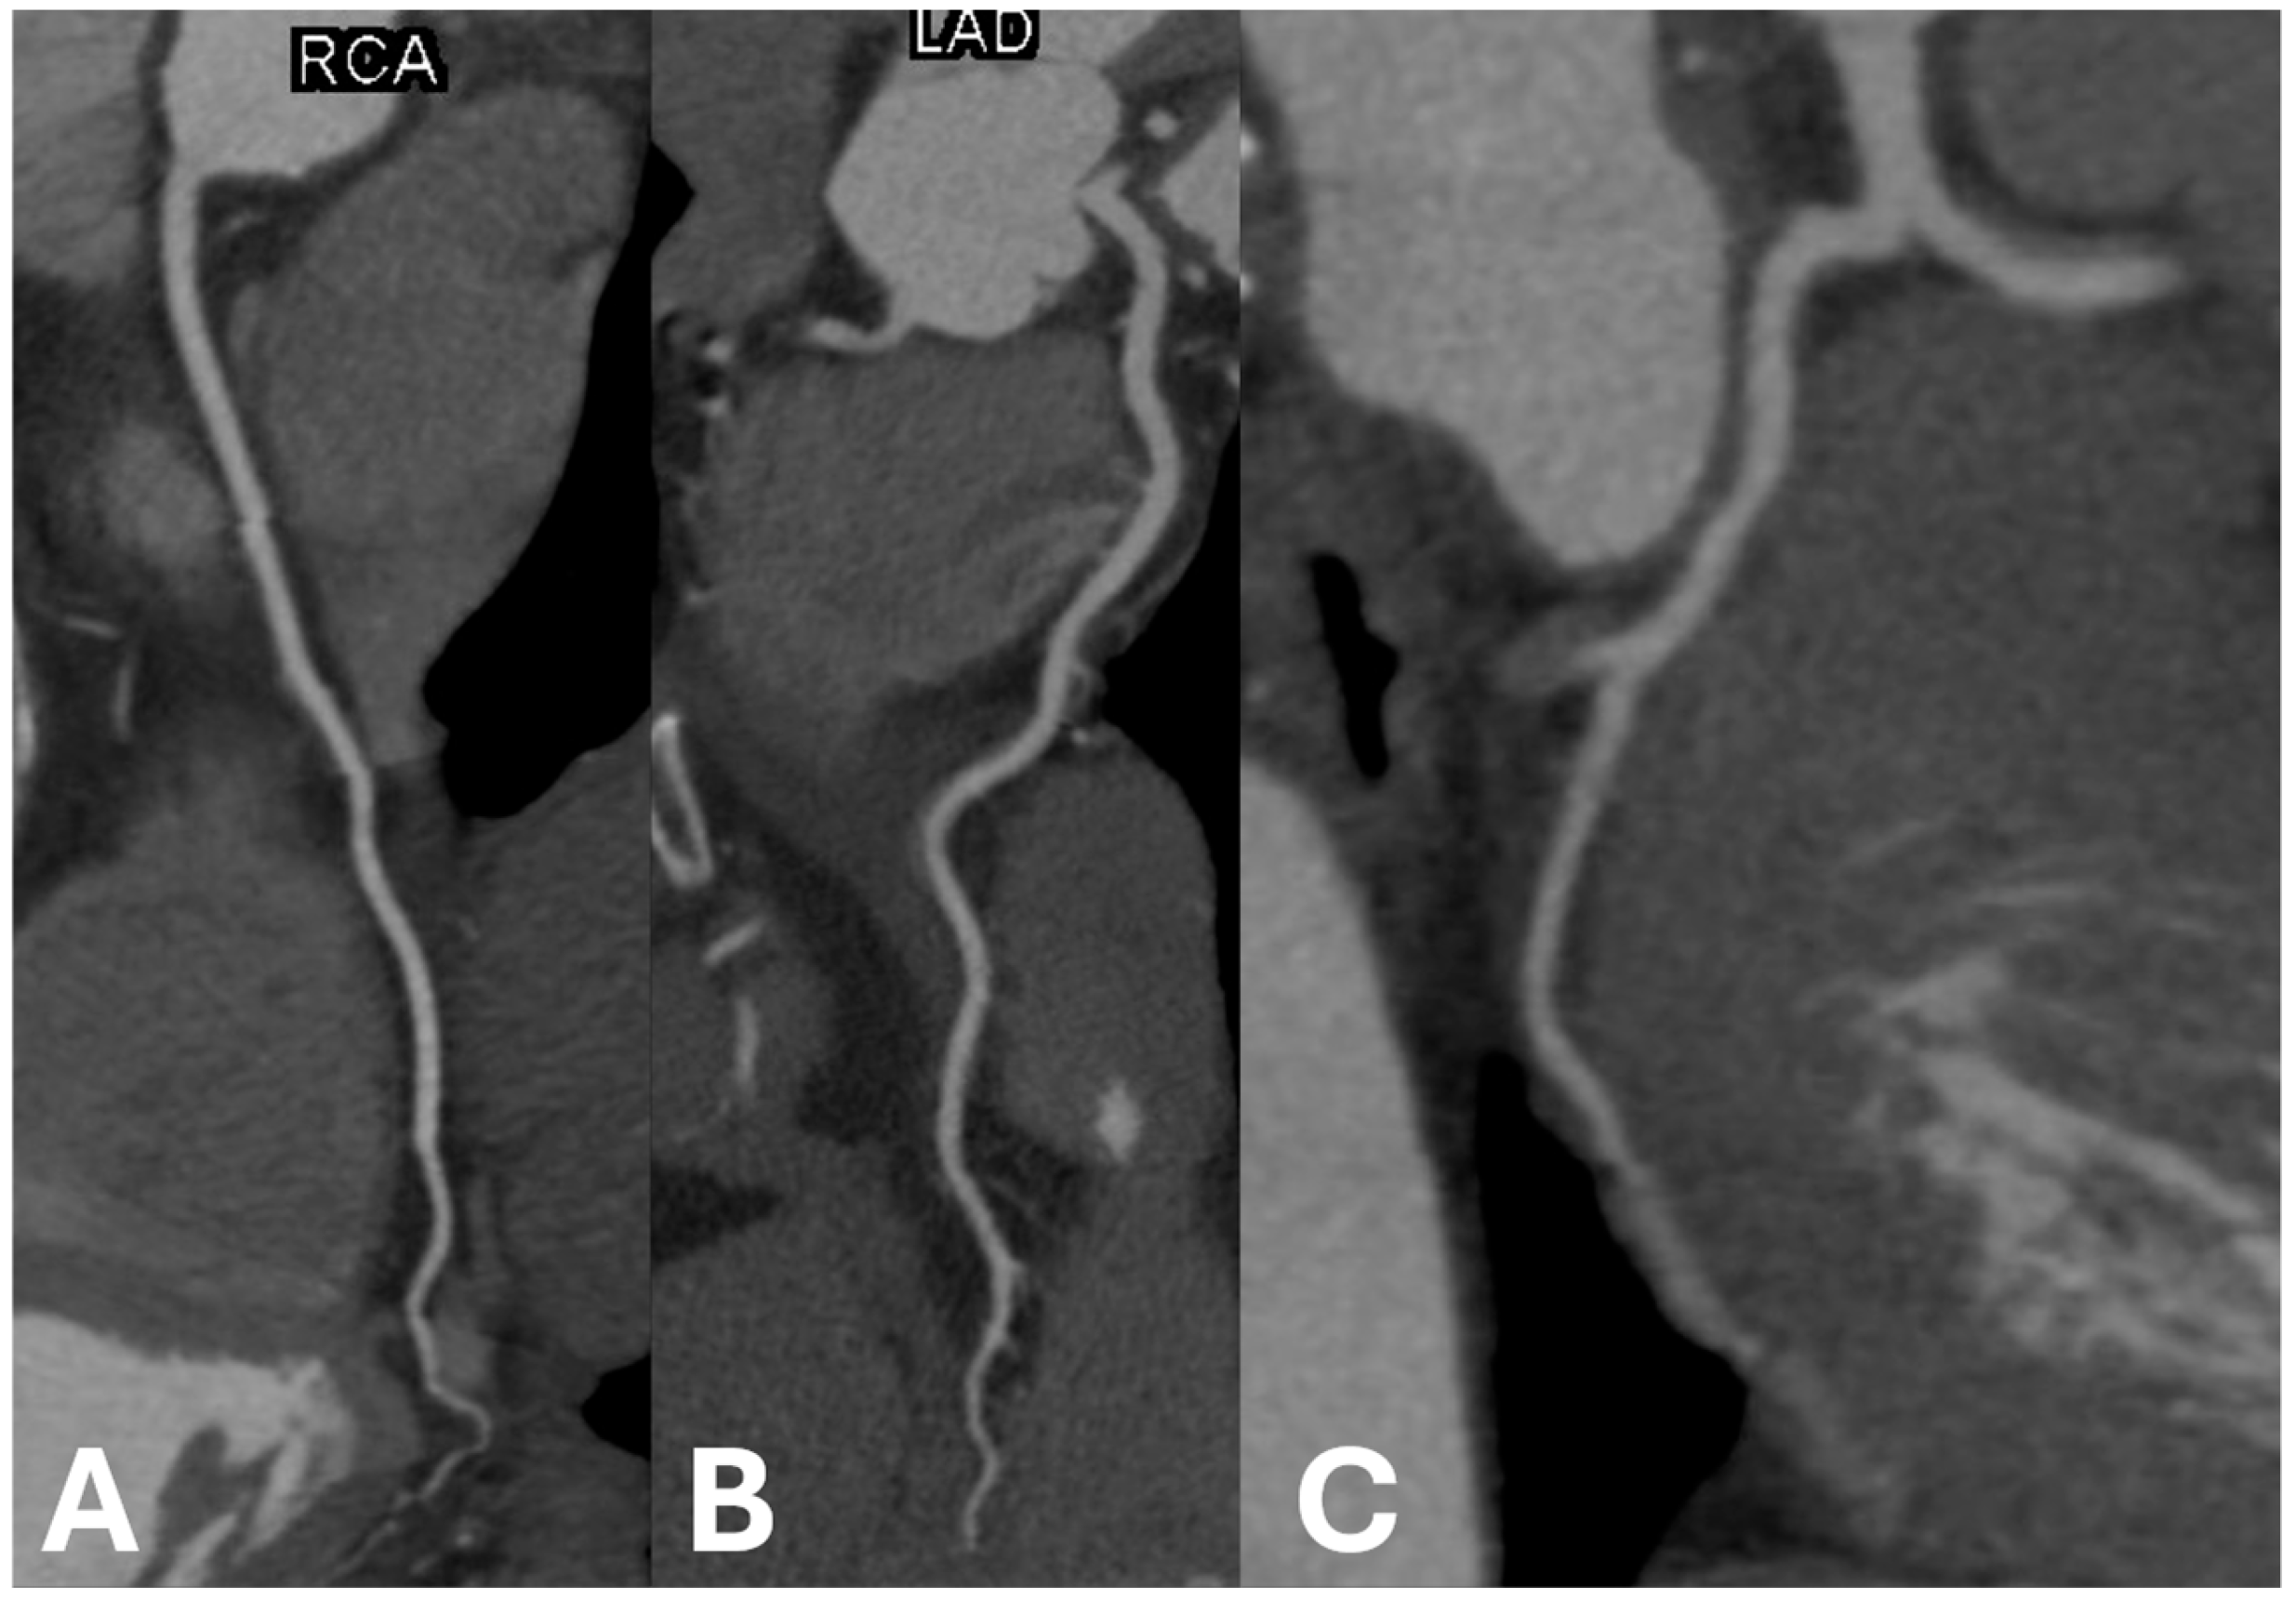

Example images of calcified and non-calcified coronary arteries are shown in Figure 1 and Figure 2, respectively.

Figure 2.

Examples of non-calcified coronary arteries in (A) right coronary artery, (B) left anterior descending artery, and (C) left circumflex artery.